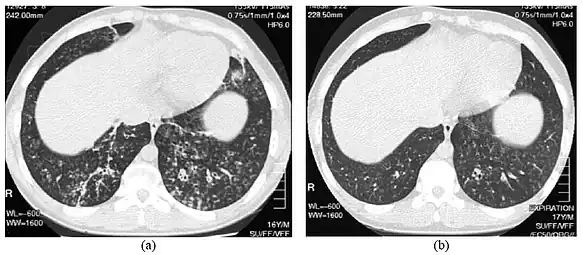

High-resolution computed tomography scan of the thorax -

High resolution computed tomography (HRCT) images of the lower chest in a 16-year-old boy initially diagnosed with DPB (left), and 8 weeks later (right) after a 6-week course of treatment with erythromycin. The bilateral bronchiectasis and prominent centri-lobular nodules with a "tree-in-bud" pattern shows noticeable improvement.